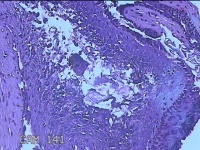

性别

男

年龄

44岁

临床诊断

皮脂腺囊肿

一般病史

右面部起疹12月,不痒。

标本名称

面部肿物

大体所见

灰白粉红色肿物0.5x0.3x0.2cm一个,表面糜烂。